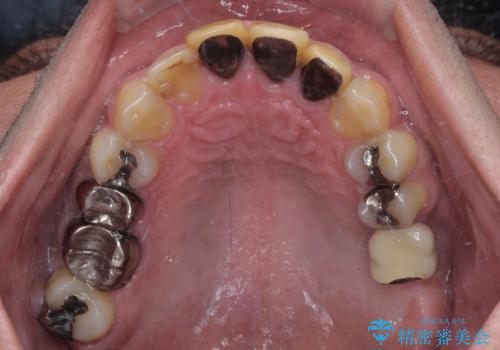

- 黄ばんだ前歯や目立つ奥歯の銀歯をきれいにしたいとのことで来院された患者様です。

欠損している歯や、割れてしまって抜歯の必要な歯などがあり、咬合力が強いため欠損部はインプラント補綴を前提に治療を行うこととしました。

しかしながら、左下の抜歯部位は骨欠損が著しく大きく、多大な垂直的骨造成を要するため、3歯を支台としたブリッジによる補綴治療とし、右下のみをインプラント補綴としました。

小さい修復物の銀歯が装着されている歯はセラミックインレーにて、その他はオールセラミッククラウンにて補綴治療を進めることとしました。